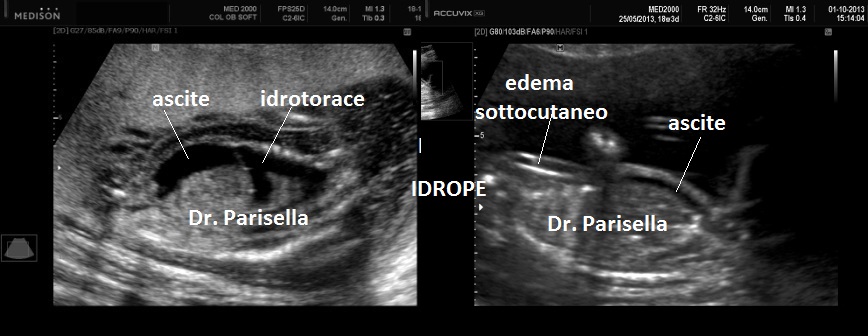

All'ecografia prenatale si riscontra ipoplasia toracica (torace stretto e coste corte), rizomelia lieve-moderata e frequentemente  displasia renale policistica.